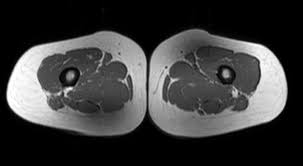

Use Of Mri For Volume Estimation Of Tibialis Posterior And Plantar Intrinsic Foot Muscles In Healthy And Chronic Plantar Fasciitis Limbs Sciencedirect

Use Of Mri For Volume Estimation Of Tibialis Posterior And Plantar Intrinsic Foot Muscles In Healthy And Chronic Plantar Fasciitis Limbs Sciencedirect from ars.els-cdn.com